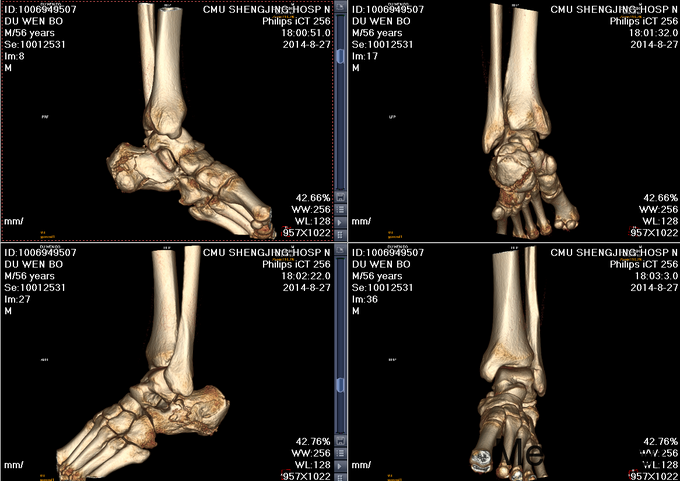

左跟骨骨折sanders2型

患者及其家属自述于2015-10-17 13:30 因在自家干活时不慎从2米高梯子上摔下,当时患者意识清醒,无法站立,左踝部疼痛、肿胀、活动受限,以“左踝部骨折”为诊断收入我科;患者伤来无发热、无头晕、恶心呕吐,无呼吸困难,既往饮食睡眠可,大小便正常; 左踝部肿胀明显,压痛阳性,左踝部活动受限,可闻及骨擦音及骨擦感;患肢皮肤感觉较健侧无明显异常,足趾可活动,足背动脉可触及;